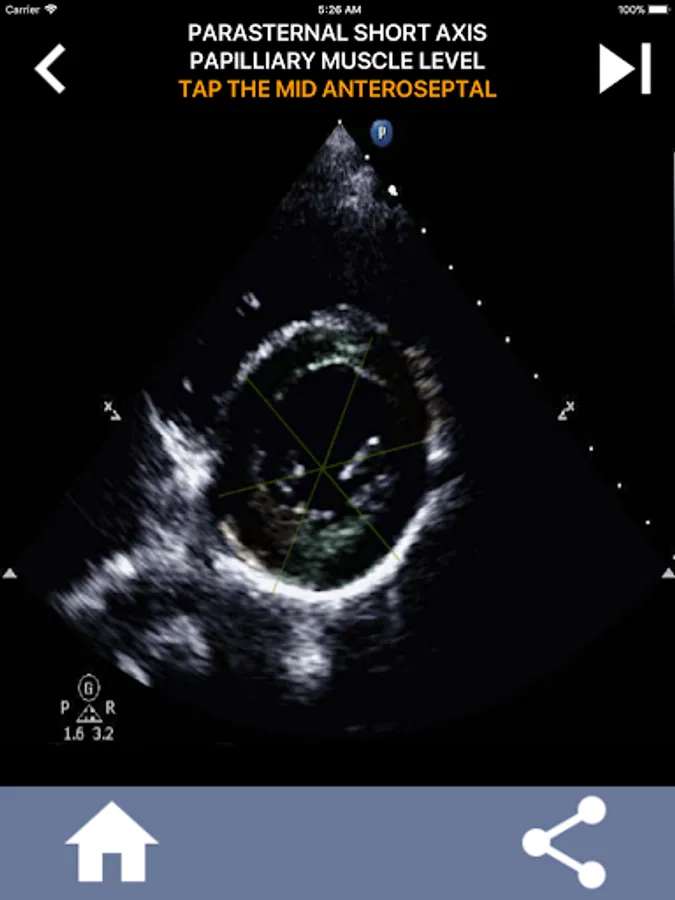

Understanding the AHA (American Heart Association) heart segments is of utmost importance for a cardiac sonographer to effectively communicate with the cardiologist who writes the report. By knowing the specific anatomical regions and their corresponding segments, the sonographer can accurately describe and communicate any abnormalities or findings, ensuring clear and concise communication between both professionals.

This understanding becomes particularly crucial when the cardiologist seeks to ascertain the precise location of a problem or when the on-call physician identifies an issue within a specific region, prompting the sonographer to accurately display the corresponding segment, such as the mid-inferior wall. Thus, possessing a comprehensive grasp of the AHA heart segments is essential skill set.

This app will test your knowlegde using actual echo images, which I often find to be the best teaching method.